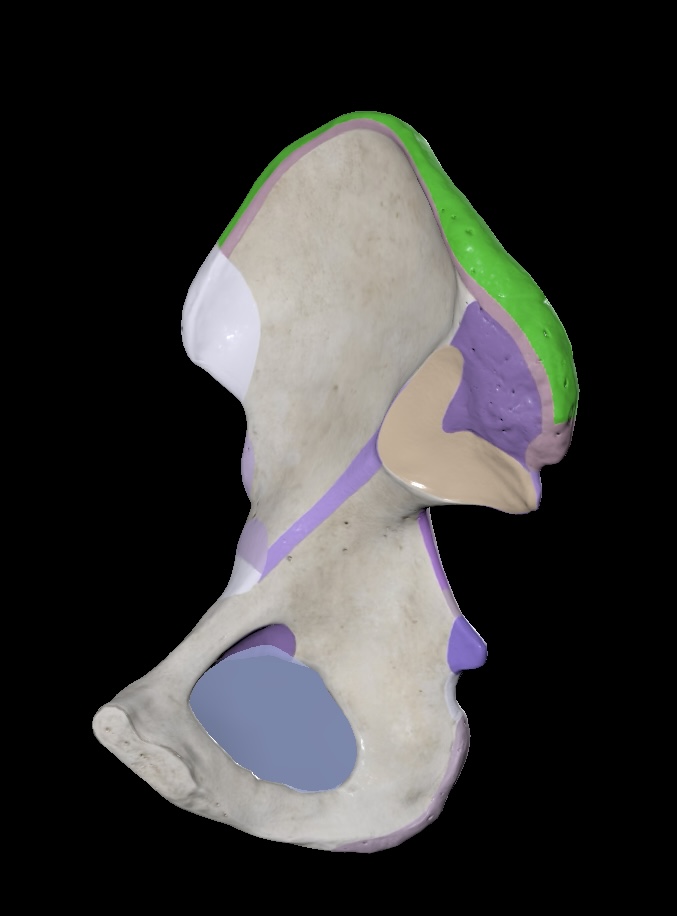

Illium

Ischium

Pubis

Ischial Spine of Ischium

Iliac Tuberosity of Illium

Anterior Superior Iliac Spine

Anterior Inferior Iliac Spine

Posterior Superior Iliac Spine

Posterior Inferior Iliac Spine

Iliac Crest

Acetabulum